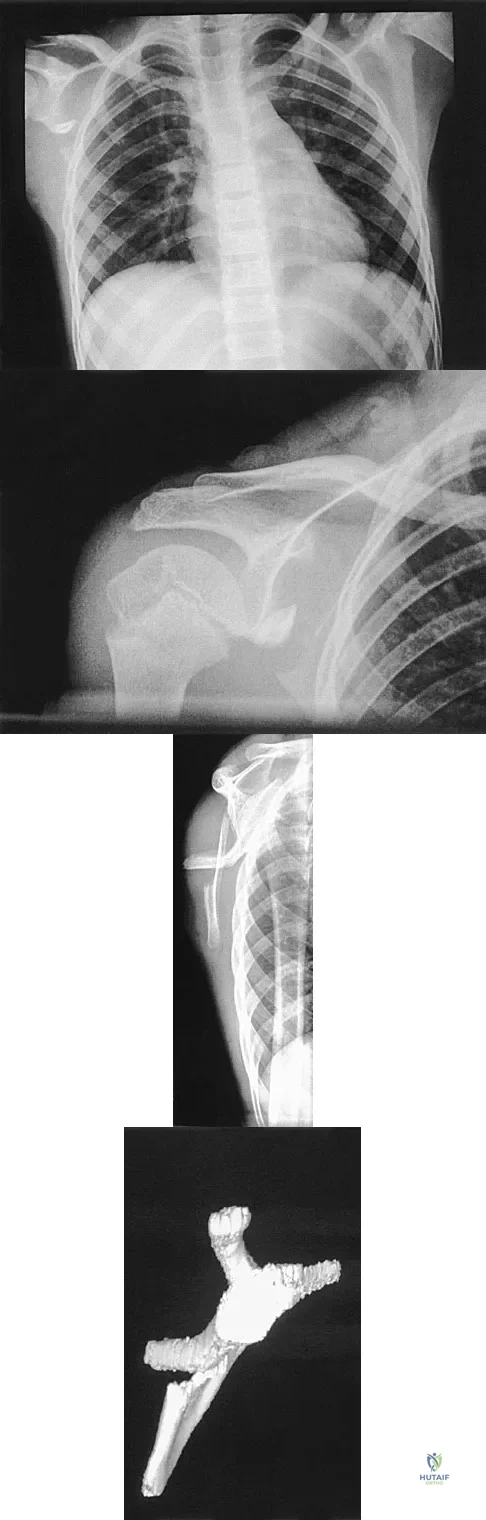

A 12-year-old boy has severe left shoulder pain after being struck by an automobile. A chest radiograph, AP and lateral radiographs, and a CT scan with three-dimensional reconstruction of the scapula are shown in Figures 38a through 38d. Management should consist of